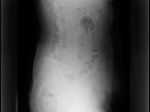

脊柱管狭窄症は、脊椎の退行性変化や変形性関節症が進行した結果、主に発症する疾患です。

脊柱管狭窄症の特徴は、脊髄及び脊髄神経根が通過する空間が狭くなることで発症します。

脊柱管狭窄症はどのような原因によって起きるのか?

脊柱管狭窄症は、脊髄の周りにある靭帯が時間の経過とともに肥大して生じます。

この中でも肥大した黄色靭帯に加えて、周りの椎間関節が骨棘を増殖させ、脊柱管の空間を圧迫します。

この肥厚性黄色靱帯及び関節の周りの骨棘によって神経を圧迫し、痛み、脱力感、神経症状、歩行困難を引き起こす可能性があります。